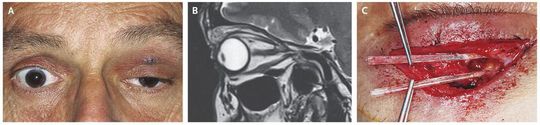

A 52-year-old man presented with ptosis and limited ocular and eyelid elevation in his left eye (Panel A). A swollen and droopy eyelid had developed after the patient collided with a school of fish while he was swimming at a Red Sea beach 4 weeks earlier. Magnetic resonance imaging revealed a granuloma in the upper eyelid and anterior upper orbital region (Panel B), with no foreign body visible. During surgical excision of the granuloma, two transparent tubular structures pointing toward the orbital apex were detected and extricated (Panel C). These foreign bodies were thought to have pinned and immobilized the levator muscle and superior rectus muscle. Taxonomic analysis identified the objects as mandibles of the halfbeak fish. Halfbeak fish, which are members of the family Hemiramphidae, are mostly surface-dwelling fish that are common in shallow and coastal waters, including such waters in the Red Sea. Within 3 months after surgery, the ptosis and the restriction of ocular motility had resolved completely.